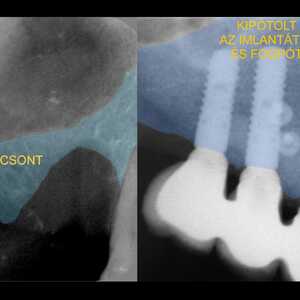

A foghúzás a mai modern érzéstelenítő anyagokkal teljesen fájdalmatlanul elvégezhető. Főként igaz ez arra a kíméletes, állcsontprezervációval (csontmegőrzéssel) egybekötött fogeltávolításra, amelyet kecskeméti fogászatunkon rutinszerűen alkalmazunk. Miért olyan kritikus a kíméletesség és az állcsontprezerváció? Mert a 21. századi fogászatban már a fogeltávolítás pillanatában, szakmailag megalapozottan kell terveznünk a későbbi fogpótlást. Ehhez pedig elengedhetetlen, hogy a foghiány helyén megmaradjon az elégséges csontmennyiség, a szép lágyrészprofil és a harmonikus ínyszél.

A hagyományos foghúzás után ez sajnos nem így történik: a csont szélessége és magassága az idő múlásával drasztikusan csökken, a csontszintet követve pedig az ínyszél is visszahúzódik. Olyan esztétikailag és funkcionálisan is hátrányos helyzet alakul ki, ami a későbbi pótlást – legyen az rögzített híd vagy fogimplantátum – komolyan megnehezíti. Hogy ezt megelőzzük, rendelőnkben már a húzáskor a jövőbeni pótlásra fókuszálunk.

A fogat rendkívül kíméletesen, hagyományos foghúzó fogó használata nélkül távolítjuk el, maximálisan megóvva a környező csontstruktúrát. Szemben a hagyományos szájsebészeti ellátással, ami mikrotöréseket idéz elő a csontban (ez pedig elkerülhetetlen csontveszteséghez vezet). Ráadásul a mi eljárásunkkal a fog helyét sem hagyjuk üresen. A fog helyét rögtön feltöltjük, így szinte maradéktalanul meg tudjuk őrizni az eredeti csontmennyiséget a későbbi tökéletes végeredmény érdekében.